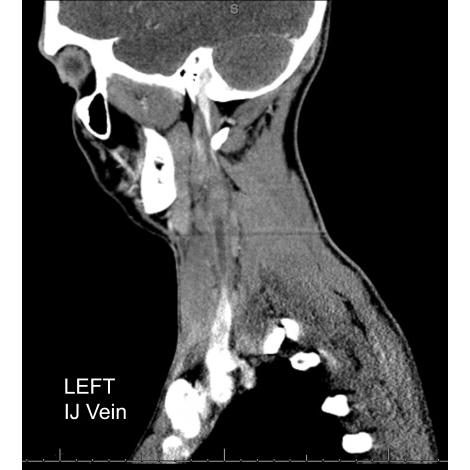

| A Pain In The Neck - Page #3 | |||